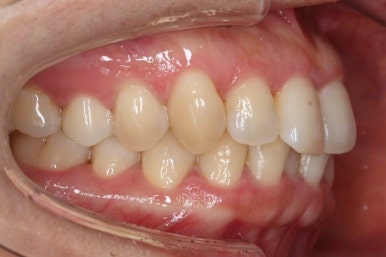

마찬가지로 부산설측교정 키다리아저씨치과에서 처음 내원하셨을 당시의 입안 모습입니다.

어금니쪽은 특별히 이상이 없었고, 위아래 앞니만 삐뚤한 상태였습니다.